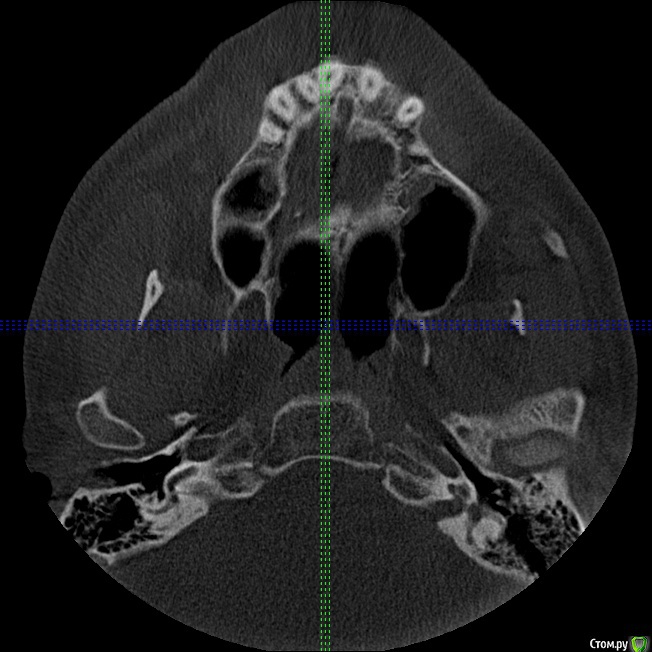

Секатор Опубликовано 4 октября, 2015 Поделиться Опубликовано 4 октября, 2015 (изменено) Здраствуйте,уже писал,но проблем много,но сча есть снимки зд(ссори за флуд).Начну издалека года два летом примерно неделю начили болеть зубы справа с отдованием в ухо и висок,оперативно ничего не делал(спас ал алкоголь),но я решил,что это 8-ки,и за зиму последнию все удалил,но отдования в висок и болезненность уха осталось,много времени прошло после удаления.Напряжение у виска и в области уха,взгляните на мою 6 справа,дно пазухи деформировано под её давлением,боли в области зуба нет-она причина?По лор все чисто,как будто болит зуб отдовая в ухо и висок,но без боли в области челюсти.Ближе к внутренней стенки пазухи и заходя на неё сформирован остроконечный конус дном пазухи,вследствии давлении корня зуба. Изменено 4 октября, 2015 пользователем Секатор 1 Ссылка на комментарий

kozloff Опубликовано 16 октября, 2015 Поделиться Опубликовано 16 октября, 2015 Поймите, с пазухой все хорошо, просто отлично, и с корнем верхнего зуба тоже. Удаляйте злосчастный мышьяк, пломбируйте каналы в пульпитом зубе и будет вам счастье! Ссылка на комментарий

IvanK Опубликовано 16 октября, 2015 Поделиться Опубликовано 16 октября, 2015 С пазухой все хорошо Меньше читайте про зубы и не надо постоянно смотреть свое кт... Хорошего дня) 1 Ссылка на комментарий